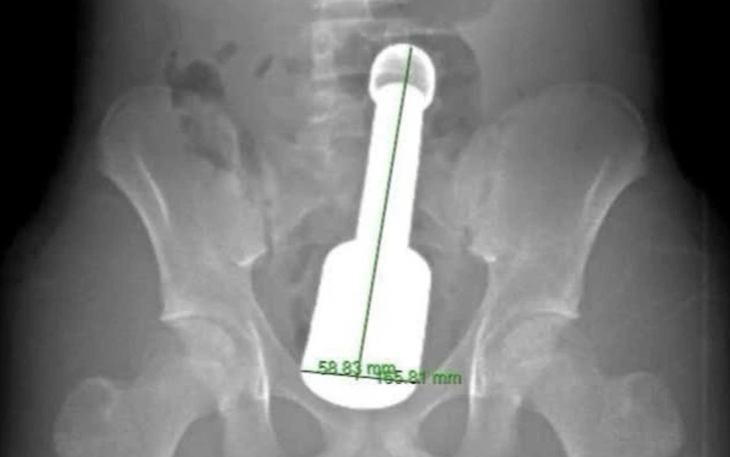

Kết quả chụp X-quang cho thấy dị vật đã di chuyển xuống dạ dày.

Bệnh nhi được gây mê toàn thân trước khi thực hiện thủ thuật. Quá trình nội soi diễn ra thuận lợi, các bác sĩ gắp thành công dị vật - một chiếc chìa khóa cửa có kích thước khá lớn so với đường tiêu hóa của trẻ, móc khóa vẫn còn nguyên.